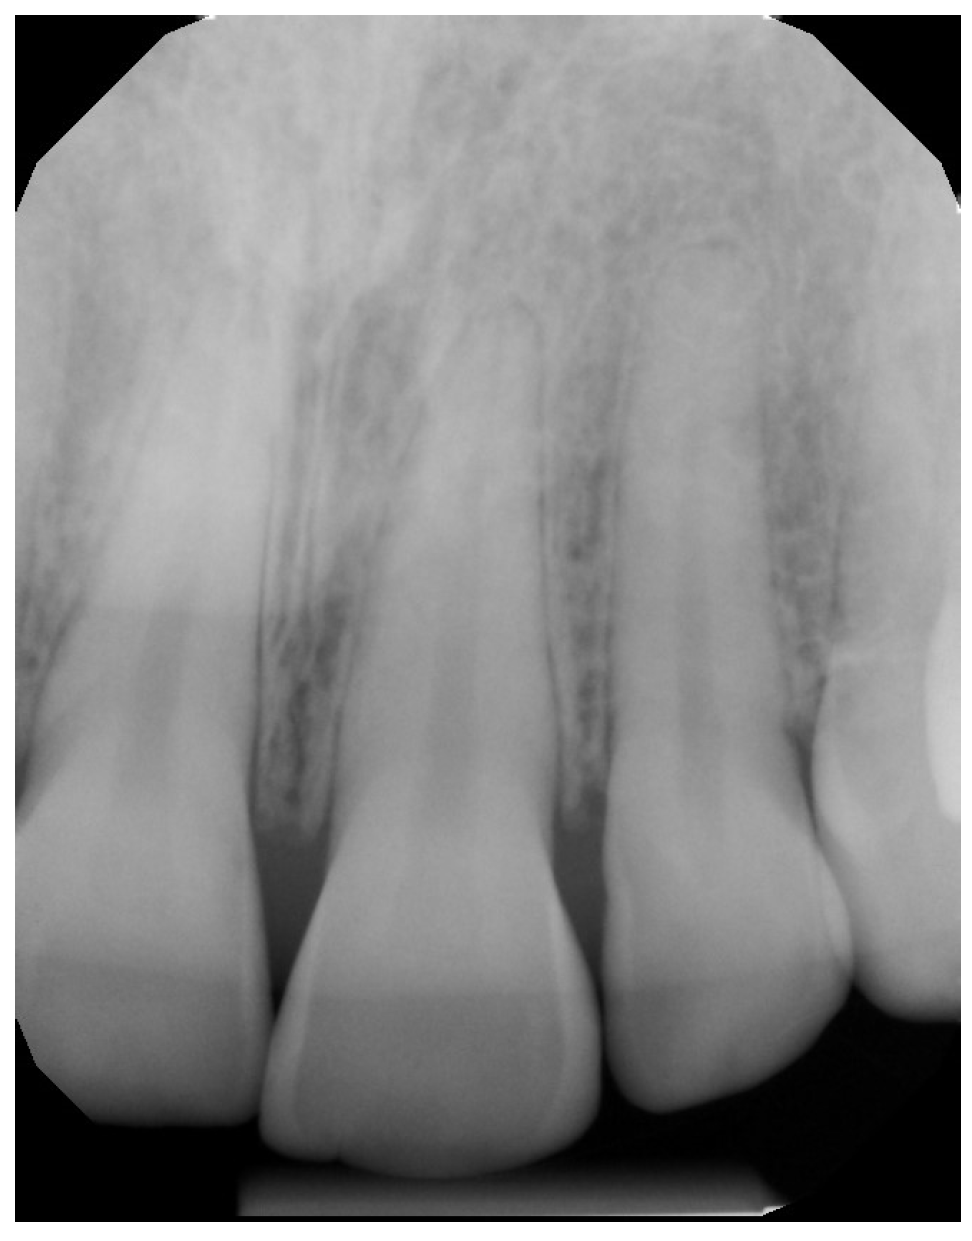

2. Case Presentation